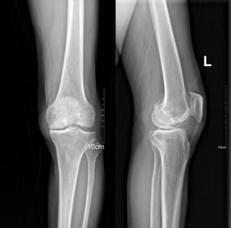

经朋友介绍,瑞安市人民医院关节外科对关节疾病的诊治在省内非常有名,10多年前就率先在浙南地区开展了单髁置换术,慕名来到瑞安市人民医院关节外科就诊。接诊的主管医生对潘阿姨进行了细致检查,发现潘阿姨的膝关节疼痛部位主要位于膝关节内侧,膝关节轻度内翻,步态轻度跛行。经X线片检查,膝关节内侧关节软骨磨损,软骨下骨骨质硬化,诊断为“右膝关节骨性关节炎”。

潘阿姨手术前X线片